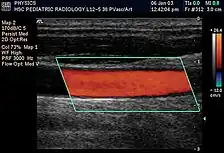

Em aplicações médicas de ultrassom, a onda detectada é frequentemente uma reflexão de tecido em movimento, como hemácias no sangue. A diferença entre as frequências contém informações sobre a velocidade do objeto. Essas informações podem ser usadas para criar mapas de fluxo sanguíneo.

Power Doppler é um método de processar o sinal que se baseia na amplitude de todos os sinais Doppler, independente da direção do movimento (ou seja, da direção do fluxo). Isso melhora a sensibilidade ao movimento, ao custo da informação da direção do fluxo. Maior sensibilidade permite a detecção e interpretação de fluxos sanguíneos muito sutis e lentos.

A ultrassonografia ou ecografia é um método diagnóstico muito recorrente na medicina moderna que utiliza o eco gerado através de ondas ultrassônicas de alta frequência para visualizar, em tempo real, as estruturas internas do organismo. Por meio de uma ultrassonografia com doppler, o médico é capaz de ver o fluxo sangüíneo nos principais vasos.